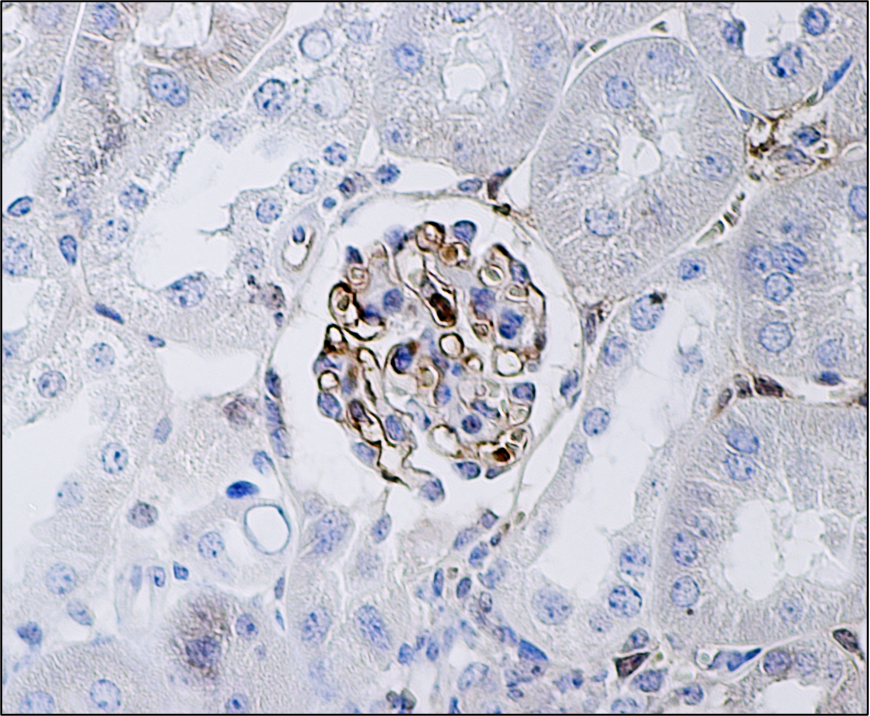

Mounting evidence supports a role for reactive oxygen species as a significant contributor to the pathophysiology of DKD, including our work showing that oxidative damage in glomeruli was characteristic in DKD susceptible mice and diabetic patients with confirmed nephropathy 1. In that study, we showed that glomerular endothelial cell (GEC) dysfunction (associated with oxidative stress and increased mitochondrial injury) precedes podocyte injury and depletion in experimental mice models of DKD susceptibility and not in resistant mice. We also demonstrated that GEC mitochondrial stress and dysfunction induced by exposure to a diabetic milieu can promote the secretion of crosstalk factors that mediate podocyte cell death in vitro 2. However, we did not know “why” this would occur only in susceptible mice. So, we built a team and took on the scientific endeavor to understand why certain strains are resilient, while others are susceptible for developing kidney disease with diabetes, and whether our findings in mice could have relevance to human genetic risk for DKD.

While exploring the molecular mechanisms involved, we determined that the risk variants were a transcription factor binding site for C/EBPβ in diabetes. An illustration of the XOR promoter variants with the predicted binding site for C/EBPβ is shown (Fig 1). C/EBPβ protein expression and nuclear localization was detected in cells in the glomeruli from DKD susceptible mice, and in vitro, it could increase Xor expression. We next asked, could C/EBPβ binding to XOR promoter variant in diabetes be involved in abnormal regulation of different cellular redox systems? To do this we captured in vivo lipid-derived free radical production in diabetic kidneys from susceptible mice, and we detected an increase in DNA 8-oxoG associated with TFAM1 in mitochondria in GECs. These results support the notion that diabetes in susceptible mice activates different redox systems; XOR and mitochondrial, and thus the sustained oxidative stress could lead to GEC dysfunction and podocyte depletion and promote DKD progression.